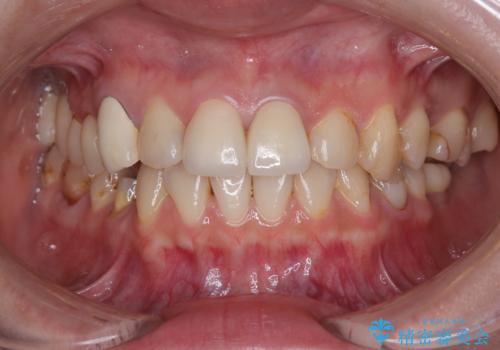

神経が露出しないよう慎重に行った結果、神経を保存することができました。処置後に多少の痛みが生じましたが、その後は良好な状態が続いています。

色、形ともに、自然な仕上がりとなり、患者様には大変満足していただきました。